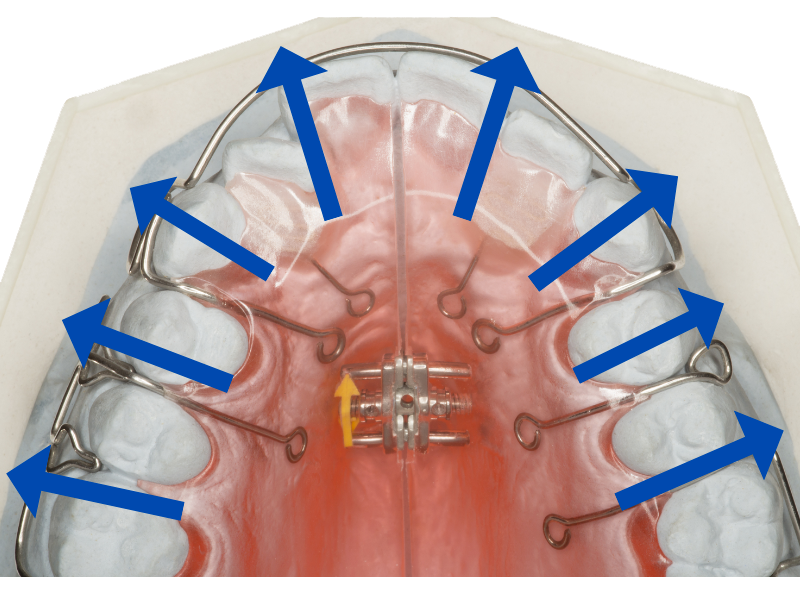

先ほどご説明した通り、小顔で顎が小さい方はスペースが足りません。そこでスペースを確保するために、前歯しか動かせない格安矯正でよく用いられるのが、拡大床という治療法です。

拡大床

ネジの力を利用して歯を外側へ押し広げることで、前歯を並べるスペースを確保します。

ただ拡大床は、歯列を広げすぎないよう細心の注意を払う必要がある、とても難しい治療法

経験不足の歯科医師では、過度に歯を押し広げてしまい、出っ歯かえって酷くなることがあります。

またこの拡大床は奥歯を左右に広げようとしますから、経験不足の歯科医師では、奥歯の位置がおかしくなってしまうことも。

そのため噛み合わせが悪くなって、食事に支障をきたす、という失敗症例もよく耳にします。